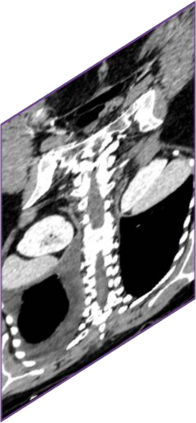

Due to the constraints of the imaging device and high cost in operation time, computer tomography (CT) scans are usually acquired with low intra-slice resolution. Improving the intra-slice resolution is beneficial to the disease diagnosis for both human experts and computer-aided systems. To this end, this paper builds a novel medical slice synthesis to increase the between-slice resolution. Considering that the ground-truth intermediate medical slices are always absent in clinical practice, we introduce the incremental cross-view mutual distillation strategy to accomplish this task in the self-supervised learning manner. Specifically, we model this problem from three different views: slice-wise interpolation from axial view and pixel-wise interpolation from coronal and sagittal views. Under this circumstance, the models learned from different views can distill valuable knowledge to guide the learning processes of each other. We can repeat this process to make the models synthesize intermediate slice data with increasing inter-slice resolution. To demonstrate the effectiveness of the proposed approach, we conduct comprehensive experiments on a large-scale CT dataset. Quantitative and qualitative comparison results show that our method outperforms state-of-the-art algorithms by clear margins.